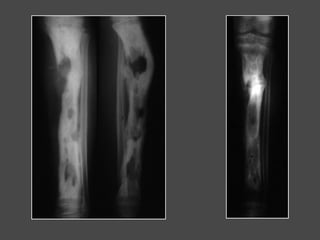

Evolución de una osteomielitis del húmero

Adolescente de 17 años

Dolores presentados después de un

juego de rugby

Luego aparición de fiebre

Brazo caliente, doloroso, inflamación

y luego fluctuación

Después de 15 días

Punción: pus

Antibiograma

Tratamiento antibiótico

Después de 15 días 20 días

Día 15 Día 20 Día 30

Día 15 Día 20 Día 30 Día 40

Necrosis y

reconstrucción

Día 45

Día 45 Secuestrectomía